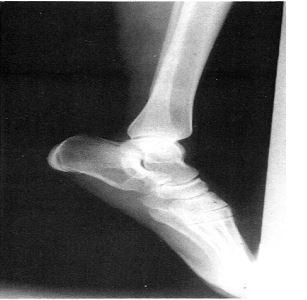

Segundo Caicoya (1982) a clínica do tumor é de dor eventual durante a caminhada associado a edema de pés. Na radiografia convencional, imagem osteolítica com bordos bem definidos e levemente escleróticas (figura 4).

Figura 4. Radiografia convencional: imagem osteolitica com bordas bem definidas. Fonte: Caicoya (1982).